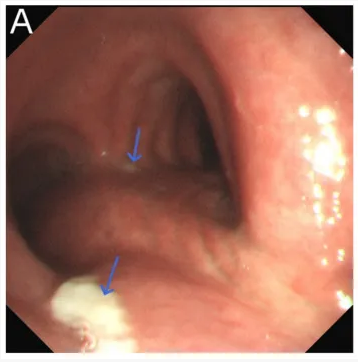

内镜下检查见气管及支气管黏膜明显充血。气管远端及右主支气管管壁覆盖少量白色物质。

床旁行胃镜检查贲门处有一大小约1 × 2.5 mm的浅溃疡,胃及十二指肠未见穿孔、溃疡及占位性病变。胃及十二指肠内可见少量气体。